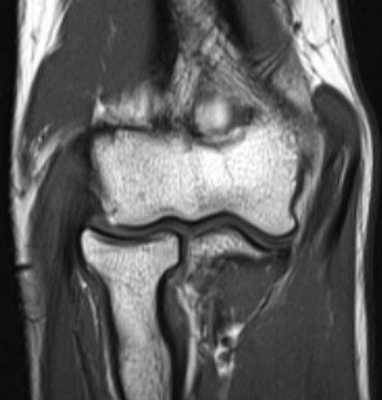

(Слева) На рисунке показана надблоково-локтевая мышца, добавочная мышца, идущая от медиального надмыщелка плечевой кости к медиальному краю локтевого отростка и проходящая над частью верхней стенки канала локтевого нерва. При этом варианте нормы локтевой нерв может сдавливаться в канале локтевого нерва, что приводит к нейропатии локтевого нерва.

(Справа) На фронтальной MPT Т1ВИ визуализируется дополнительная надблоково-локтевая мышца, медиальнее локтевого отростка.

(Слева) На осевой MPT Т1ВИ у этого же пациента визуализируется надблоково-локтевая мышца, образующая верхнюю стенку локтевого канала кзади от медиального мыщелка плечевой кости Локтевой нерв находится в локтевом канале и может быть сдавлен, что приводит к нейропатии локтевого нерва.

(Справа) Осевая MPT Т2 ВИ у этого же пациента на этом же уровне подтверждает, что надблоково-локтевая мышца соответствует сигналу от нормальной мышцы на всех частотах, что свидетельствует об идентичности.